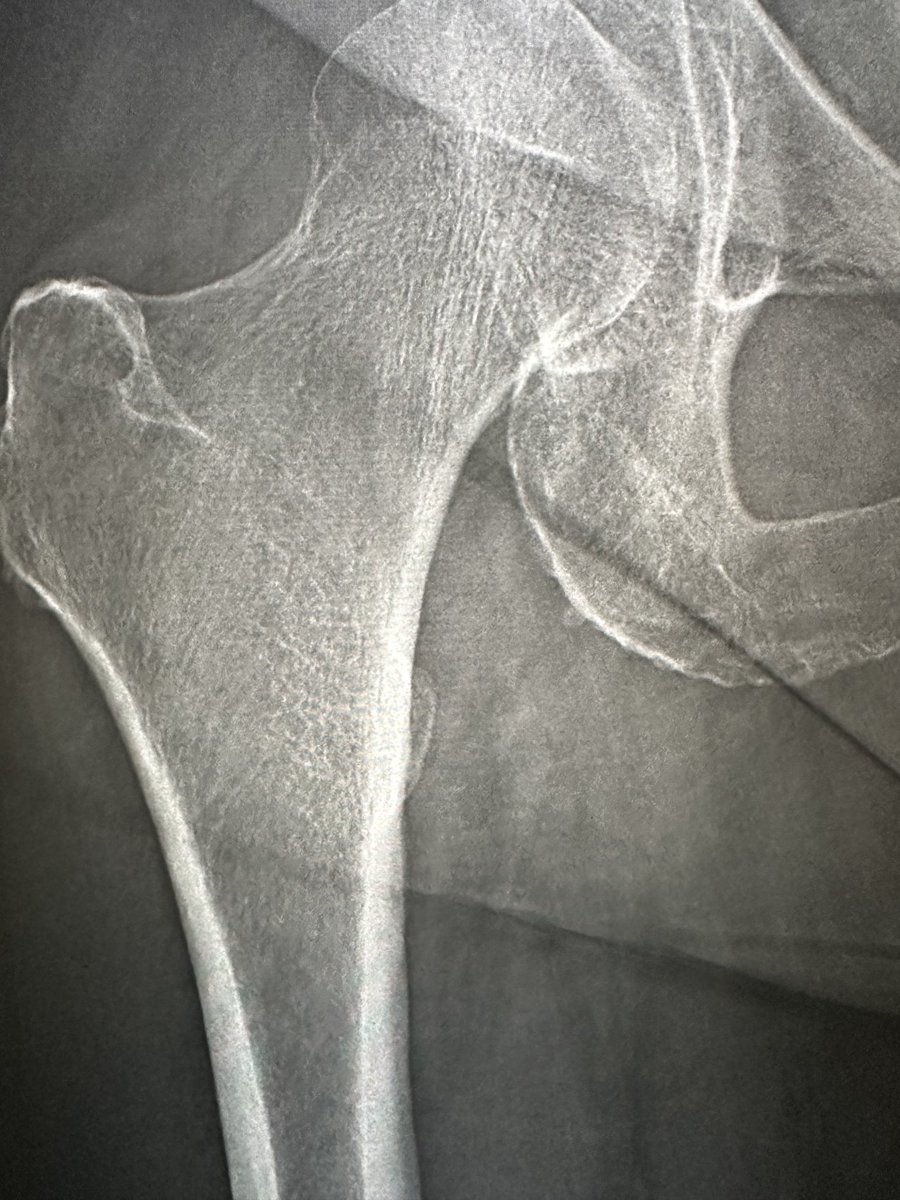

Female 67 y/o - THA

*Approach?

*What stem do you choose?

*Comments & tricks?

@AAHKS_YAG @AAHKS_YAG @JArthroplasty @AAOS1 @CleClinicArthGp